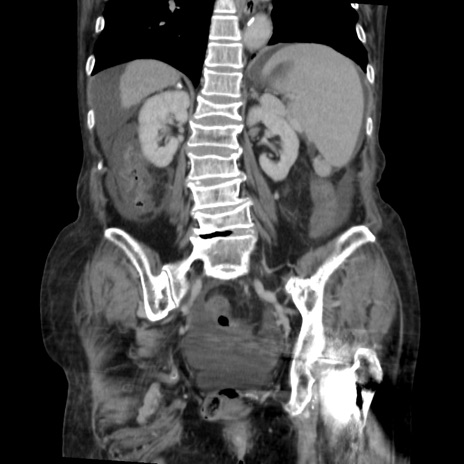

症例31(冠状断像)

【症例】80歳代 女性

【主訴】腹部膨満感

【現病歴】他院にて肝硬変にてフォロー中。1週間前から便秘、腹部膨満感、臍部腫瘤あり受診となる。

【既往歴】肝硬変

【身体所見】腹部膨隆あり、皮膚変化なし、疼痛なし。

【データ】WBC 4600、CRP 0.25